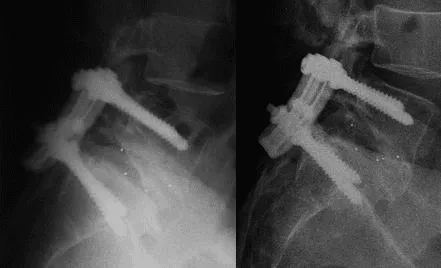

- Implant Misplacement: The screws, rods, and cages used to stabilize the spine must be placed with precision. If a screw is misplaced, it can irritate a nerve or fail to provide adequate support, potentially requiring another surgery to correct it.